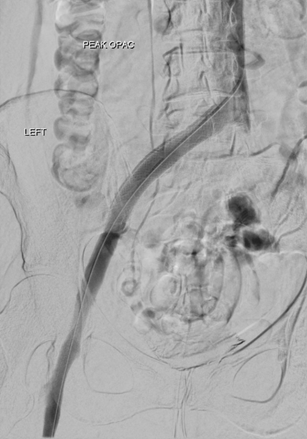

Mujer de 27 años de edad. Factor de riesgo: pastilla anticonceptiva. Refiere 7 días con dolor en la pierna y descoloración. Empeoramiento de la hinchazón. Tras la examinación, se detecta una diferencia de tamaño de 6 cm entre los muslos.

Venografía por CT de la VFC izquierda que demuestra una baja atenuación y la hinchazón de la vena femoral común izquierda en comparación con el lado derecho normal.

Angiograma inicial de la  VFC izquierda donde se indica una TVP considerable (decúbito prono).

Solent de AngioJet utilizado en el modo de Rapid Lysis isovolumétrico con 20 mg de tPA en 180 cc de solución salina normal.  Dos pasadas en total durante 8 minutos.

Venas ilíacas izquierdas tras AngioJet. Resultado excelente que muestra la permeabilidad de los vasos.

Tras AngioJet, la vena ilíaca quedó completamente sin trombos y se aprecia una clara indicación de estenosis venosa (síndrome de May-Thurner).

Wallstent de 14/90 mm  con el balón inflado a 14 mm con 14 atm. Posición y expansión satisfactorias.

Las exploraciones finales demuestran un excelente flujo en el sistema ilíaco y femoral tras la trombectomía venosa con  AngioJet  y la colocación de Wallstent.

Gerard O’Sullivan, University College Hospital, Galway, Irlanda  (abril de 2015).